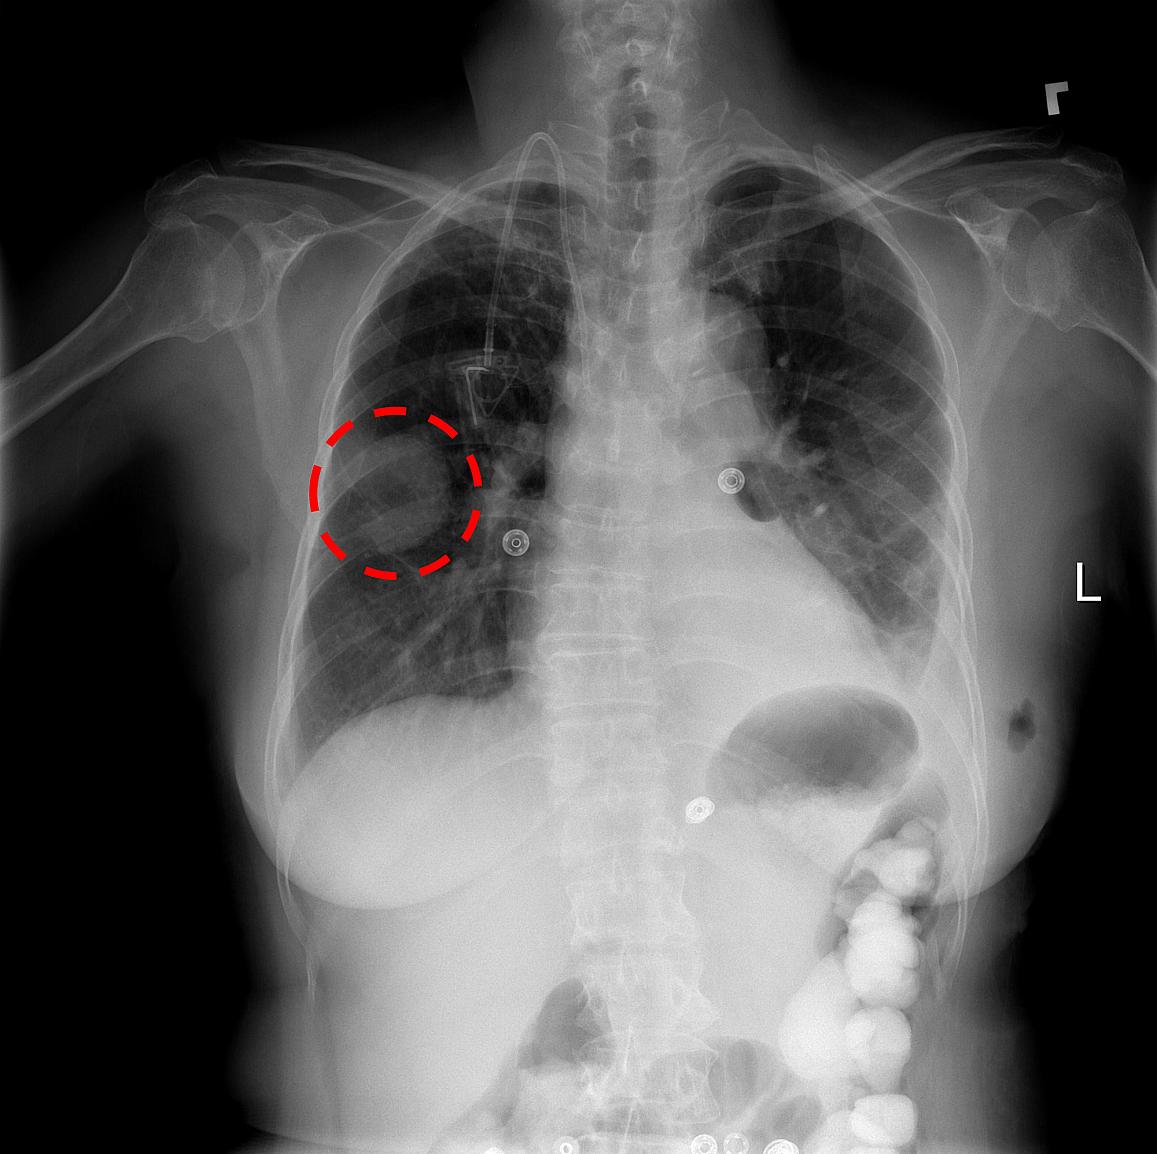

The urgent care X-ray cost varies depending on the area of the body being examined. Because urgent care clinics routinely receive fewer patients than ERs your wait to see a physician and get your arm chest or leg in front of an Xray machine is much shorter. An urgent care chest X-ray is used to identify abnormalities or diseases involving the airways bones heart lungs and blood vessels in the chest.

An urgent care chest X-ray is used to identify abnormalities or diseases involving the airways bones heart lungs and blood vessels in the chest. What does Patient First treat. With digital X-rays and full-time radiologic technologists your MedExpress medical team can quickly diagnose a range of conditions from broken bones to kidney stones.